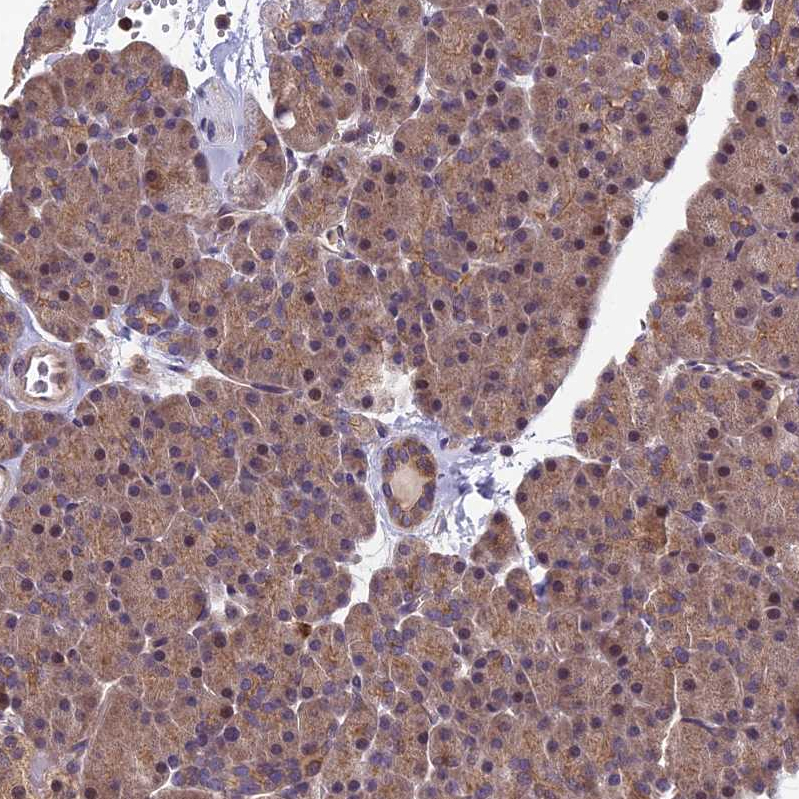

Immunohistochemical staining of human pancreas shows strong cytoplasmic positivity in exocrine glandular cells.